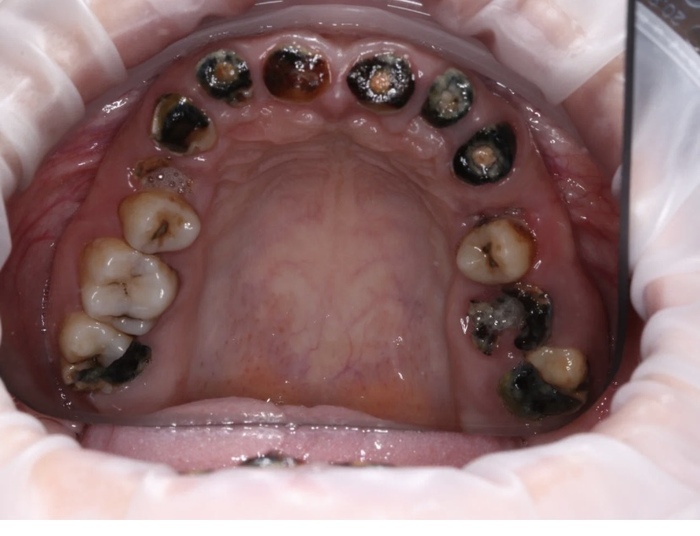

Вот так выглядело до удаления в начале пути после спиливания неудачных имплантов :

Вот так перед этой самой операцией: